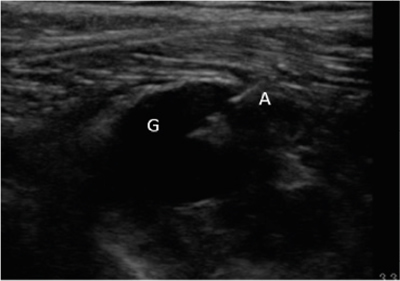

Este artículo presenta el caso de un paciente de 69 años con una neuropatía compresiva peronea secundaria a un ganglión, inicialmente interpretada como una radiculopatía L5. Este incorrecto enfoque supuso la sobremedicación del paciente, un mal control algésico, la realización de una discectomía L4-L5 innecesaria y una pobre evolución neurológica.

Un enfoque diagnóstico correcto y un abordaje terapéutico precoz habrían supuesto una mayor mejoría clínica e incluso una recuperación neurológica completa del paciente. Por ello, este caso sirve para resaltar: a) el valor de la ecografía en neuropatías periféricas como herramienta diagnóstica y pronóstica y el de la ecografía en gangliones como arma diagnóstico-terapéutica; b) el uso de las pruebas diagnósticas como apoyo a una exploración física exhaustiva, y no como diagnóstico en sí mismas, y c) la importancia de la publicación de casos no positivos para optimizar recursos, evitar repetir errores, reducir el sesgo de publicación y facilitar el inicio de proyectos de investigación.

Figura 1

Figura 2